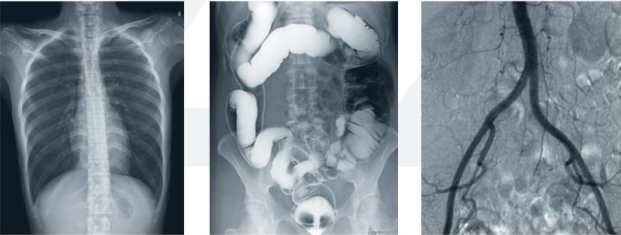

數(shù)字平板胃腸機(jī)屬于多功能X線機(jī),除具有傳統(tǒng)胃腸機(jī)所有功能外,還有DR平板探測(cè)器X線攝影所有功能,主要用于消化道對(duì)比造影、消化道吞咽造影、全脊柱拼接攝影、全下肢拼接攝影、ERCP、泌尿系造影、“T”管造影、鋇劑灌腸、四肢造影、子宮輸卵管造影等各類檢查,是檢查消化道潰瘍、腫瘤、異物等疾病的主要方法之一。

數(shù)字平板胃腸機(jī)不僅可以做普通的胃、食管鋇餐透視,胸腹部的常規(guī)透視檢查,而且圖像更清晰,多了數(shù)字化處理過(guò)程,還可以實(shí)時(shí)點(diǎn)片,更便捷的獲得實(shí)時(shí)圖像,及時(shí)抓拍住病灶圖像,為患者留存影像資料。這就像我們的手機(jī)抓拍瞬間圖像保存到手機(jī)相冊(cè)一樣,能夠診斷早期食道癌、胃癌、小潰瘍等疾病。